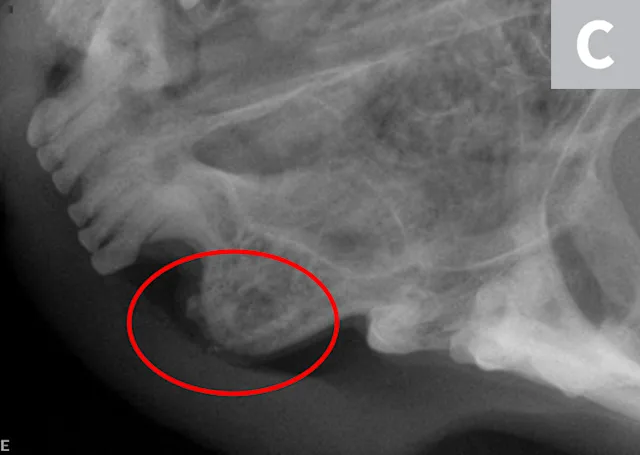

A complete oral examination and full-mouth dental radiographs were performed with the patient anesthetized. The detailed oral examination confirmed unhealed extraction sites with sharp crown fragments protruding from the alveoli into the oral cavity. In addition, an advanced TR lesion was noted affecting the left maxillary third premolar tooth (Figure 3). Dental radiographs confirmed advanced type 2 resorption affecting all involved teeth, as well as oral extension of the remaining tooth structure (Figure 4).

Teeth with type 2 TR have undergone significant replacement resorption. In these cases, the lost root structure is replaced by bone. Therefore, teeth with type 2 TR have a different radiographic density as compared with normal teeth. Radiographic findings typically include areas with no discernible periodontal ligament space (ie, dentoalveolar ankylosis) or root canal. In advanced lesions, there is little to no discernible root structure (ie, ghost roots).

Crown amputation is an accepted therapy only in appropriately selected cases in which dental radiographs confirm the following:

Advanced type 2 resorption

No periodontal ligament

No endodontic system

No evidence of periodontal disease

No evidence of endodontic pathology